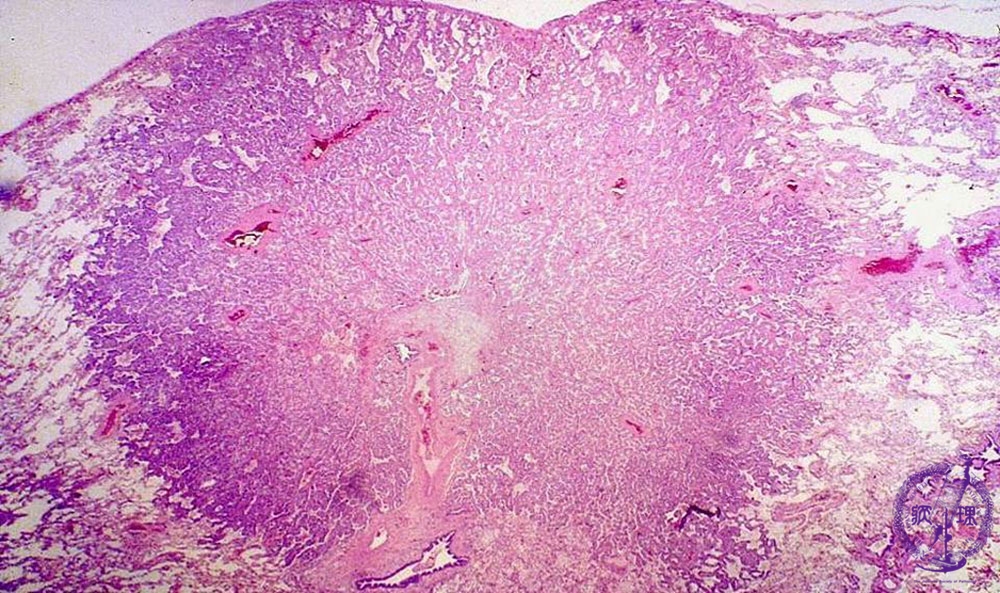

• š(17)Non-small cell lung carcinoma(adenocarcinoma)

Microscopic view (HE stain, low power view): Adenocarcinoma of lung. In small-sized tumors, the histology is relatively uniform whereas in larger tumors, histology is apt to be diverse.